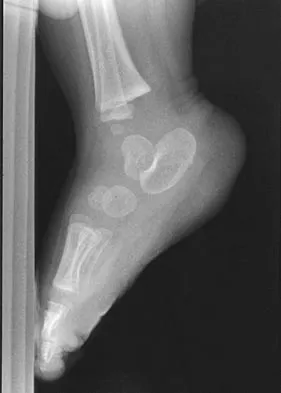

Figures 38a and 38b show the CT scans of a 64-year-old woman. What is the most likely diagnosis?

Explanation

The CT scans show large cystic lesions in the talus and calcaneus with complete subluxation of the subtalar joint, allowing the calcaneus to slide laterally until it becomes blocked by the fibula. The cause of this subluxation is severe posterior tibial tendon dysfunction. Although no fibular fracture has yet appeared, it can occur with continued stress from the calcaneus. There is, however, a pathologic fracture in the medial calcaneus through a medial degenerative cyst. The joint space is irregular and not symmetrical as would be seen in an inflammatory arthropathy. Cystic lesions are not present in the tibia. No stress fracture is seen in the talus. Coughlin MJ: Sesamoids and accessory bones of the foot, in Coughlin MJ, Mann RA (eds): Surgery of the Foot and Ankle, ed 7. St Louis, MO, Mosby, 1999, pp 437-499.